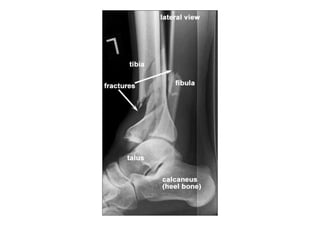

RADIOLOGIA DO

TRAUMA DO ESQUELETO

Referência: http://www.accessexcellence.org/RC/VL/

figura